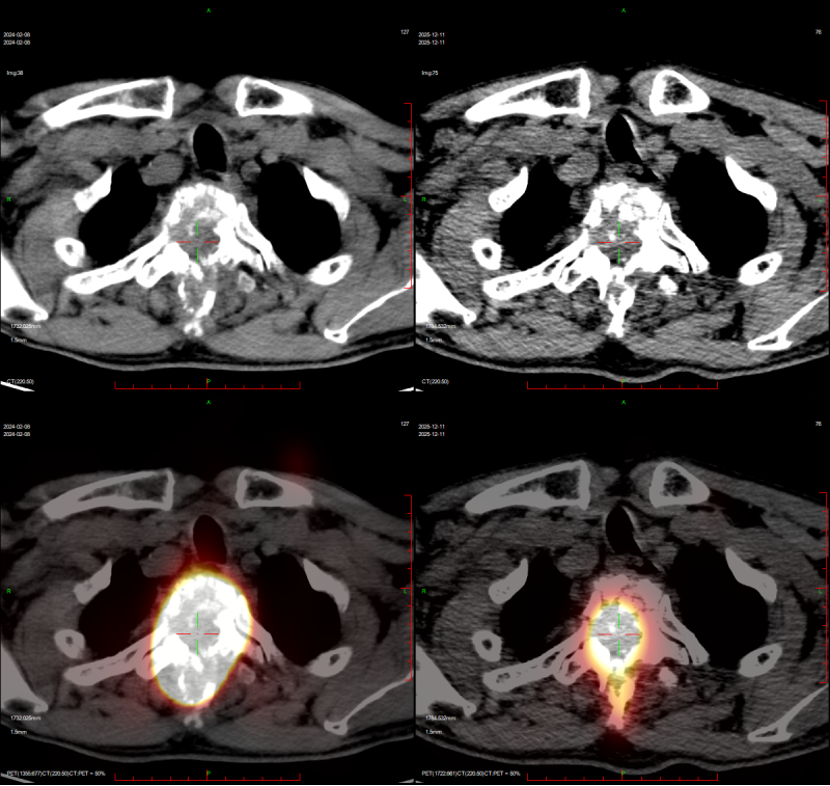

胸椎转移瘤伴脊髓压迫治疗后,病灶缩小

治疗过程比林伯想象的简单多了:就像喝普通盐水似的,一口喝下“药水”,然后在核素防护病房里隔离一段时间,等辐射衰减达标就能出院。随着治疗推进,奇迹慢慢发生:林伯感觉腿上有了知觉,原本麻木的双腿渐渐能轻微活动,再后来,在侄子的搀扶下能坐起来,最后竟能拄着拐杖慢慢走路了!复查显示,他胸椎上的转移灶明显缩小,脊髓压迫减轻,神经功能在逐步恢复。